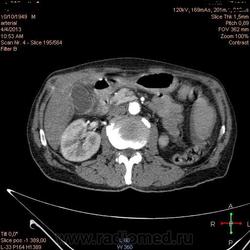

Здравствуйте, коллеги.Помогите разобраться.Пациент 1949 г беспокоять боли в животе , отсутствие аппетита, похудание .За неделю пожелтел, ослаблен.Нужно исключит кацер головки подж.железы.Анализы сегодня сдал еще не готовы.УЗИ зак увеличение л\узлов у ворот печени.Образов головки подж.железы ?На КТ жировой гепатоз.вроде головка подж железы не увеличены.

Мне надо исключить или поставить образование головки подж.железы.Хирурги ждут заключение, хотять оперировать.

Даже если вы пропустили малый рак панкреас, пациент умер не из-за него - желтуха не механическая, а, вероятней, паренхиматозная.